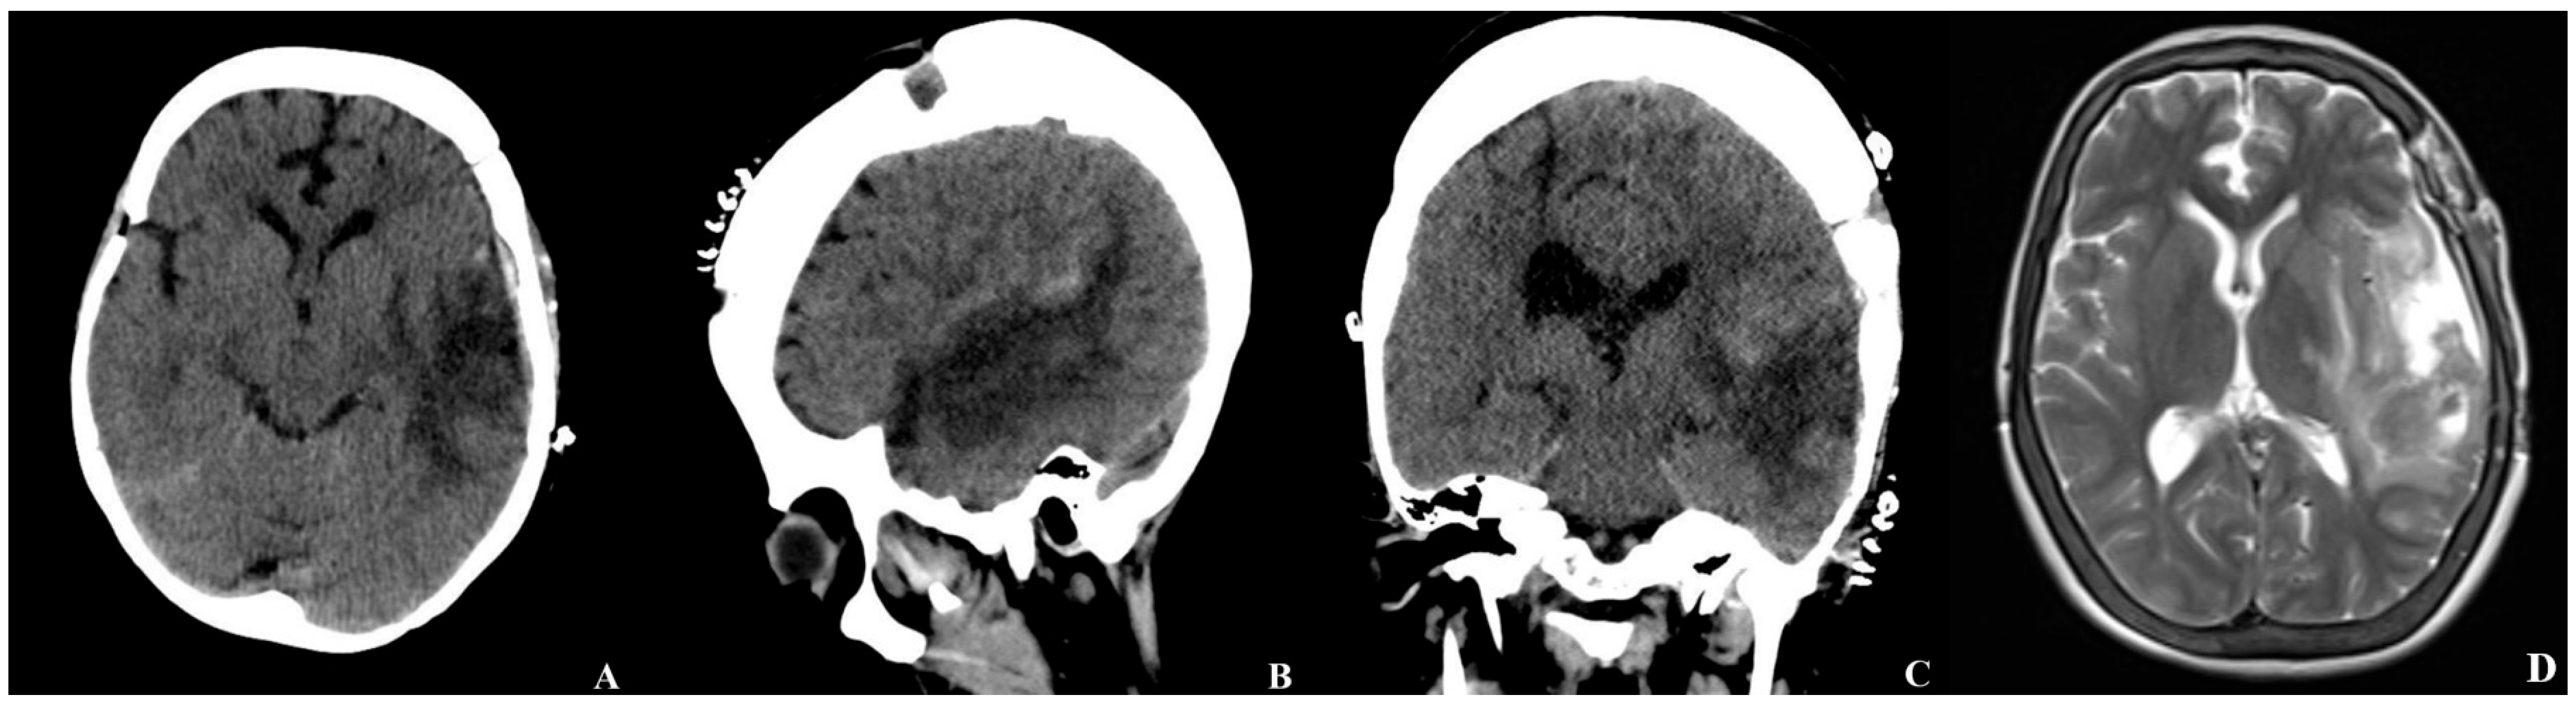

An emergent brain CT demonstrated a 48 mm × 75 mm intraparenchymal hematoma in the left temporal and insular lobes, with a 16 mm midline shift to the right, as well as multiple burr hole defects (Figure 1).

Figure 1. Initial brain CT obtained at the patient’s presentation to the emergency department ((A) axial, (B) sagittal, (C) coronal view). The scan demonstrates a large intraparenchymal hematoma in the left temporal and insular lobes, accompanied by a significant midline shift to the right and mass effect with compression of the adjacent ventricular structures. Multiple burr hole defects from the previous revascularization procedure are also visible.